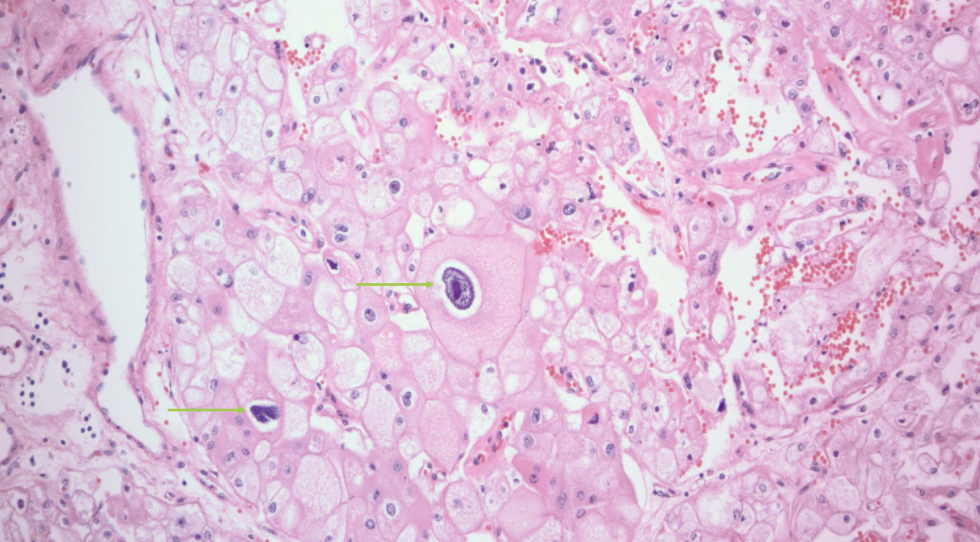

chromophobe RCC

arise from intercalated disc of collecting ducts; multiple chromosome loss and extreme hypodiploidy

chromophobe RCC

RCC with best prognosis

chromophobe RCC

raisinoid nuclei